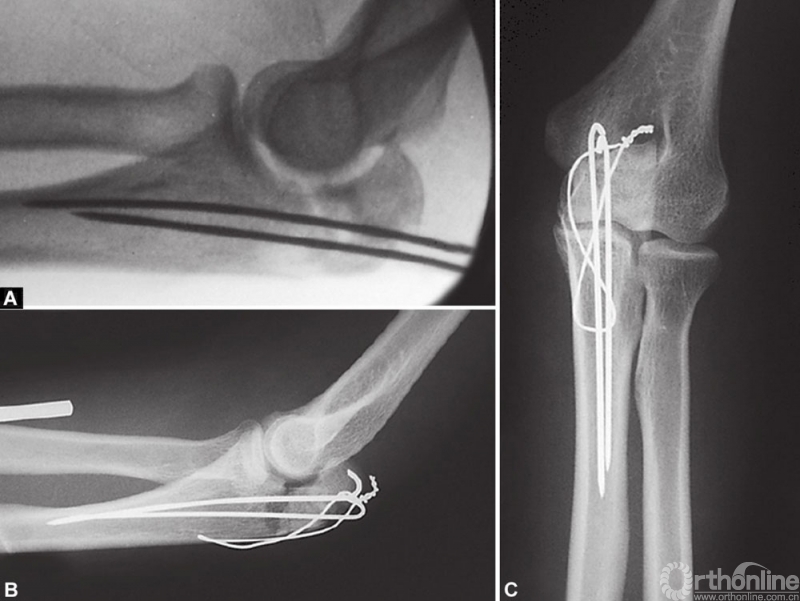

张力带钢丝将循环张力负荷转换为对骨折端的动态压缩力。这样,当患者活动肘关节时骨折端产生压应力,压应力促使骨折断端间产生的摩擦力能够维持复位直至骨折愈合。(图2A和B)显示了张力带钢丝固定简单横形鹰嘴骨折的良好作用,但不是斜形或粉碎骨折。

图2 A和B示意图展示了张力带钢丝治疗简单横形鹰嘴骨折的工作原理(A)对照斜形骨折(B);在图A中,伸肌和屈肌的拉力在骨折断面产生压缩力以维持复位,而图B中剪切力将导致骨折移位

“8”字钢丝环应该放置在三头肌腱下面,而不是绕在克氏针的近端周围。使用宽口径导针可以使钢丝顺利穿过。在远端,钢丝环穿过2mm钻头在骨折线远端2~3cm钻的一个孔。钢丝环在鹰嘴尖端的近端拧紧,尾部剪断,弯曲并埋入肱三头肌腱下。钢丝应避免在尺骨边缘皮下拧紧和打结,否则会造成损害和不适。除了有经验的外科医生,术中常规用X线片检查关节的一致性和植入物的位置。